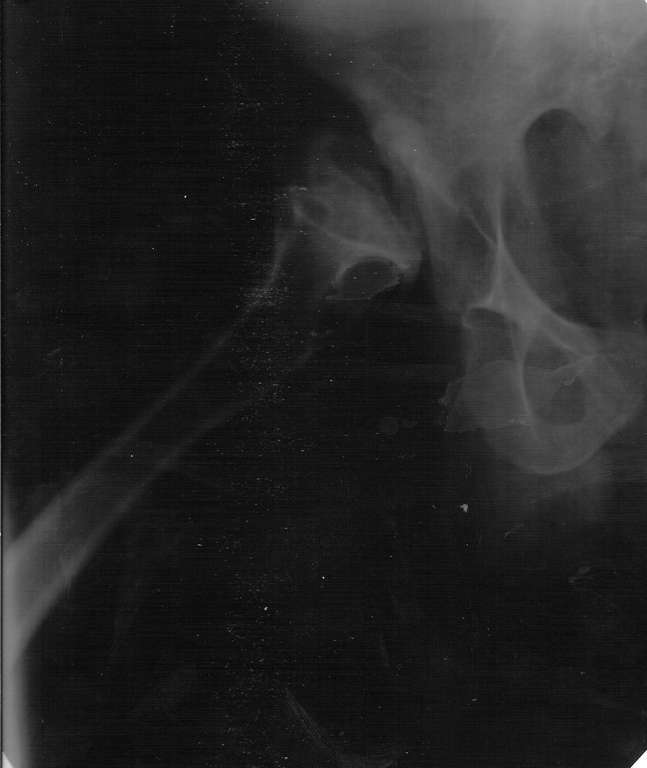

Здраствуйте, Уважаемые коллеги! Хотел бы вынести на обсуждения интересный случай. Больной 26 лет, наш коллега, с рождения диагноз Псевдохондродисплазия (карлик).

4 года назад начали беспокоить суставы, особого внимания не придавал - купировал болевой синдром. Недавно обратился с следующей картиной на рентген - снимках, имеется одинаковое укорочение обеих н/конечностей правой за счёт ас. некроза головки, левой - из-за варусной деформации голени.

- нужно-ли эндопротезирование т/б, коленных суставов

- нужна-ли пластика крыши и дна вертлужной впадины